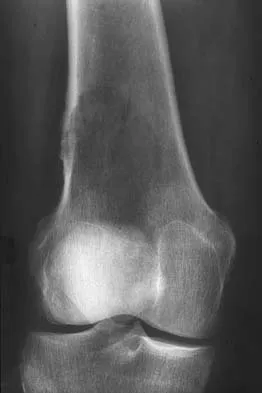

Question 10

A 23-year-old man who was the restrained driver in a car involved in a high-speed motor vehicle accident sustained the closed injury shown in Figures 32a through 32c. Which of the following factors has the greatest impact on the risk of osteonecrosis?